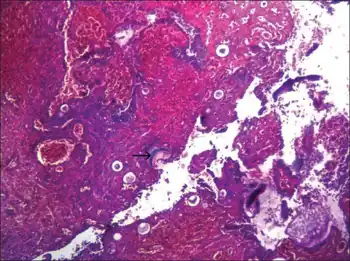

Infection

This organism infects the mucosa of the nasal cavity, producing a mass-like lesion. This mass appears to be polypoidal in nature with a granular surface speckled with whitish spores. The rhinosporidial mass has been classically described as a strawberry-like mulberry mass. This mass may extend from the nasal cavity into the nasopharynx and present itself in the oral cavity. These lesions commonly cause bleeding from the nasal cavity.